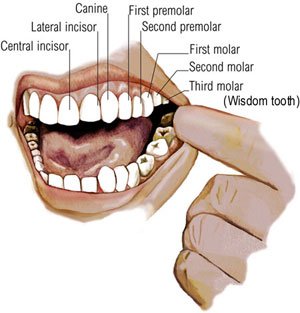

Hello there good people, I’ve been a bit “kurang sihat” these past two days. You see, I got one of my “molars” (the 2nd “molar” on the top left side, see pix) pulled out and as a result (actually once the anaesthetic injection worn off) my body temperature shot up; all of a sudden I was down with “demam” and I can’t do anything for days.

Hello there good people, I’ve been a bit “kurang sihat” these past two days. You see, I got one of my “molars” (the 2nd “molar” on the top left side, see pix) pulled out and as a result (actually once the anaesthetic injection worn off) my body temperature shot up; all of a sudden I was down with “demam” and I can’t do anything for days.

After a bit of probing into my mouth, and an x-ray, Dr. Gerald said I have two choices. The 1st option is to keep that tooth (part of the wall crumbled already lah) which means I can do “root canal” (to deaden the nerves) and reconstruct the tooth to its former glory. The other choice is to just pull it out and get it over and done with, in short “kill the fukking fukker lah!”